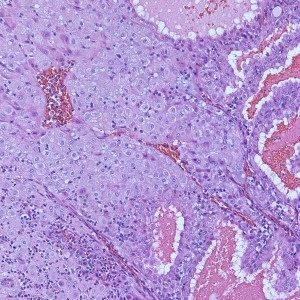

At low power we see throughout the specimen that numerous enlarged hydropic chorionic villi are present (circles).